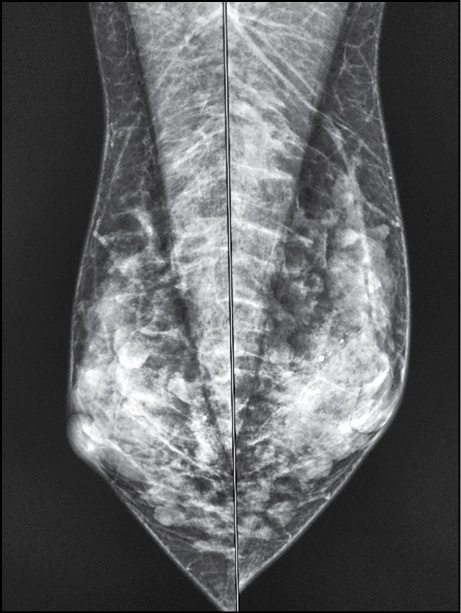

A 38-year-old patient complained of 1-month itching of the right nipple and skin discoloration. Breast ultrasonography and mammography findings (Figs. 5 and 6) were normal. The breast was examined by contrast-enhanced MRI. The early postcontrast series revealed a right nipple mass homogeneously accumulating a contrast agent (Fig. 7). A parametric map showed a nipple mass with rapid contrast enhancement and subsequent elimination, a type III graphic curve (Fig. 8). Morphological verification revealed nipple adenoma.

Figure 5. A nipple adenoma: mammography (mediolateral oblique projection).

Figure 6. A nipple adenoma: mammography (craniocaudal projection).

Mammography is the most sensitive technique for detecting calcifications. In the NAC, calcifications are uncommon and usually benign, such as cutaneous, calcified intraductal detritus, and calcifications due to fat necrosis. Microcalcifications can be seen in relation to intraductal carcinoma, sometimes associated with Paget’s disease. [10] Mammography is less sensitive than ultrasonography because of the greater density and mobility of this part of the breast. [11]

For mammography, the breast must be positioned correctly. [10] The nipple must be located tangentially at least in one projection, ideally in both craniocaudal and mediolateral projections. In patients with inverted nipples (normal variation), nipples should be tangential and symmetrical.

Case 2 demonstrates the complexity of the diagnostic search in a nipple adenoma. Ultrasonography and mammography revealed no abnormalities, and the correct diagnosis was established only by MRI followed by biopsy. A nipple adenoma (erosive adenomatosis or subareolar papillomatosis) is a rare variant of intraductal papilloma. Clinical manifestations include a small palpable nodule under the skin of the nipple, which is usually associated with inflammatory nipple changes (pain, redness, and swelling). Skin involvement results from the growth of glandular epithelium toward the skin surface. Skin manifestations are similar to Paget’s disease, squamous cell carcinoma, eczema, psoriasis, or infection. Histological verification is the gold standard for definitive diagnosis. Mammography and ultrasonography usually do not provide valuable information. Ultrasonography may show a hypoechoic nodule in the nipple or subareolar region. [22]